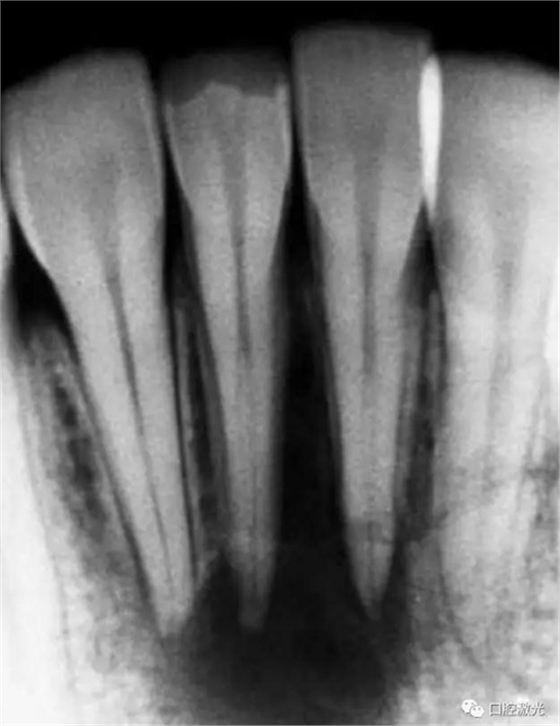

41 治療前X光片

激光治療中

6個(gè)月后治療效果